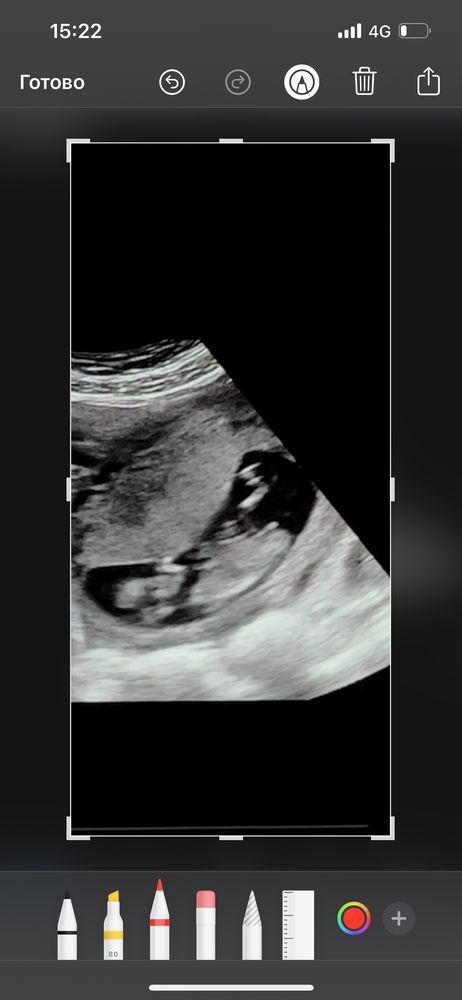

Всем привет 🤍 сегодня была на узи! 12,5недель, у меня есть 3 сына! ждём 4 малыша! Который 4,5 года к нам не приходил! сегодня снимала видео со скрининга, и думаю может можно что-то разглядеть?)) прилагаю скрины с видео , вид с боку и снизу 🤍 Благодарю за участия

Половой бугорок видно хорошо, он "торчит" практически параллельно телу, это же девчуля🥰

Похоже на девочку. Процентов на 80, как любят говорить врачи. Если на фото половой бугорок, то он параллельно позвоночнику